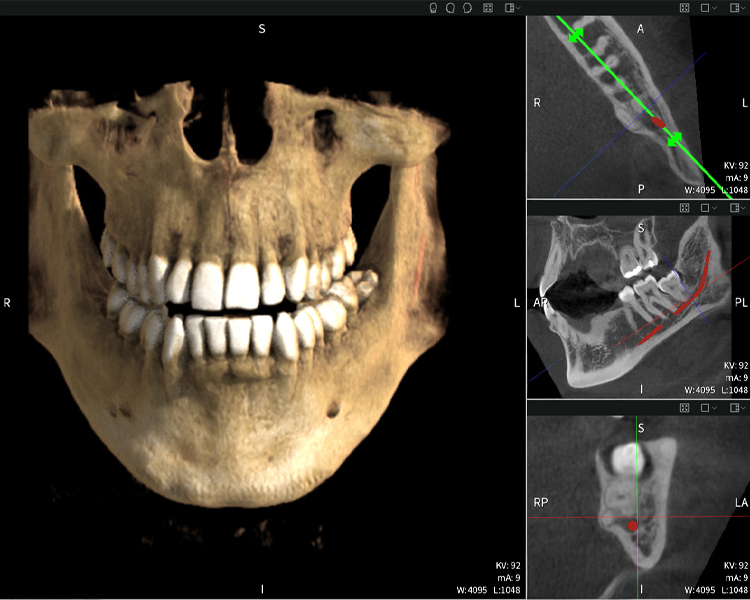

Figure b: Imaging results of Seethrough Max, in front of a black background.

Figure b

Figure d: Imaging results of Seethrough Max, in front of a black background.

Figure d

Figures b–d show various views of a 3D reconstruction of the mandible, providing a comprehensive overview of the mandibular anatomy, the position of the nerves in relation to the teeth, and allowing assessment of tooth symmetry and alignment.

Figure d shows the previously treated tooth 48, with its crown removed, and its roots left in proximity to the nerve, illustrating the high risk of nerve damage.